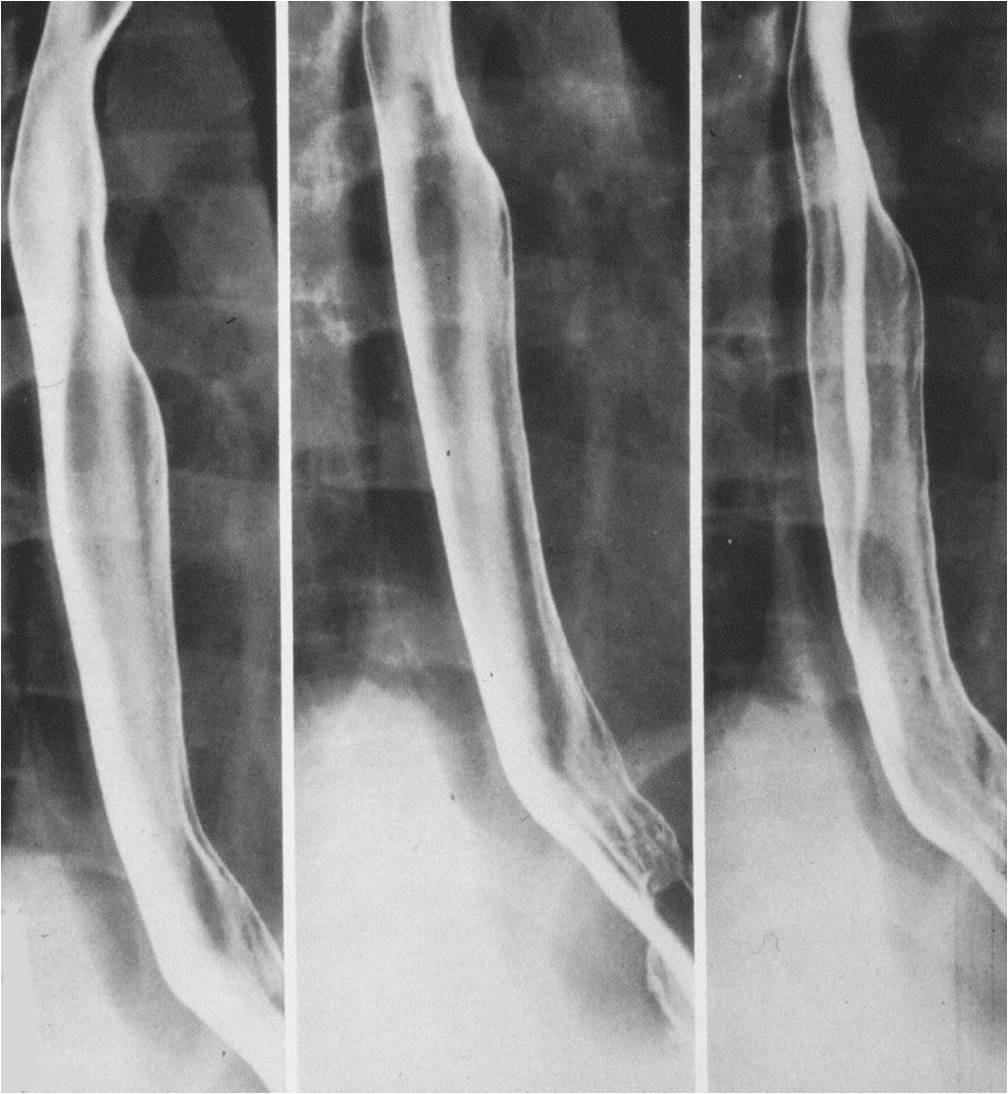

Esophageal stenosis:

Frequently, it is a complication of esophageal inflammation, which causes narrowing of the esophageal lumen. The degree of narrowing can be so severe that the lumen almost completely obliterated by scarring. It may also occur due to corrosive effect of acid or alkali indigestion as well as in reflux disease or precipitated by long term duodenal tube placement. Irritation of the esophageal mucosa causes inflammation. Alkali indigestion usually results in more severe injury as it causes colliquative necrosis in the deep wall layers, while after acid indigestion the mucosal surface is covered with a fibrotic crust which prevents deeper penetration of the corrosive agent. In addition to the stricture inflammatory diseases are also complicated by esophageal shortening, thus part of the fornix is pulled up into the mediastinum. Frequently, in patients with reflux esophagitis the stricture only involves the cardia sparing the esophagus; still a shortened esophagus could be detected.

Image

Fig.4.: Esophageal stenosis

Radiographic findings: A long segment, sharp contoured esophageal stricture is detected. Due to stiffness of the fibrotic wall no peristaltic activity can be seen. Differentiation from tumors can be difficult, thus patient history is important. Tumors cause slowly progressing dysphagia, but generally involve shorter segments.